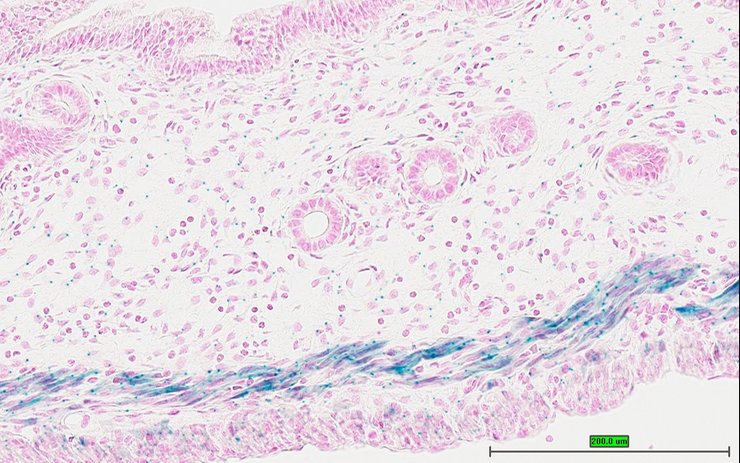

Specimen UC Davis_1889934: postnatal adult; Ptprstm1b(KOMP)Mbp/Ptprs+ (more )

Structure Level Pattern Image Note

TS28: skin Present UC Davis_1889934

Specimen UC Davis_1889935: postnatal adult; Ptprstm1b(KOMP)Mbp/Ptprs+ (more )

TS28: skin Present UC Davis_1889935

TS28: skin Present UC Davis_1889994

Specimen UC Davis_1889995: postnatal adult; Ptprstm1b(KOMP)Mbp/Ptprs+ (more )

TS28: skin Present UC Davis_1889995

Specimen UC Davis_1889996: postnatal adult; Ptprstm1b(KOMP)Mbp/Ptprs+ (more )

TS28: skin Present UC Davis_1889996